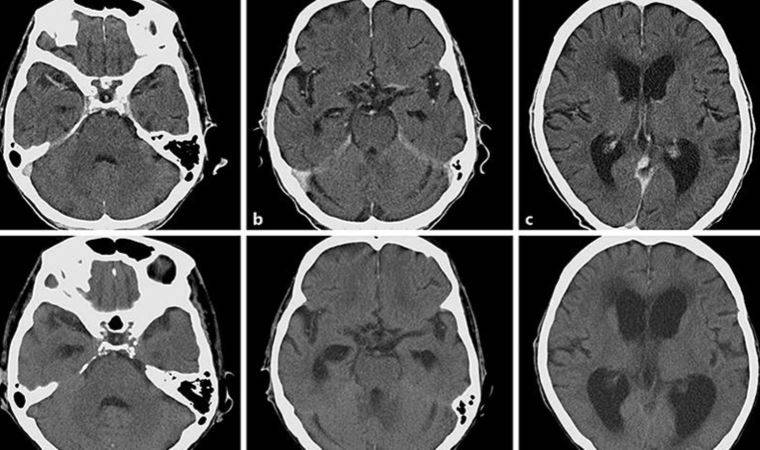

Çocuk Sağlığı ve Hastalıkları Uzmanı Dr. Hasan Çetinkaya, beyin zarı iltihabına menenjit, beyin dokusu iltihabına ise ensefalit adının verildiğini ve bu iki durum beraber ortaya çıktığı durumlara ise Meningoensefalit adını verdiklerini belirterek, “Bakteri ve virüsler çoğunlukla bu duruma neden olur. İçinde bulunduğumuz sonbahar-kış döneminde çocuklarda dirençli ateş-öksürük, orta kulak ve akciğer enfeksiyonları sıkça görülürken, beraberinde meningoensefalit şüpheli çocuklarda da artış izlenmektedir. Çocukta ateş, kusma, ishal, iştahsızlık, halsizlik, baş ağrısı, kas ağrıları, döküntü, bilinç bulanıklığı, uyku hali ve havale gibi şikayetler görülebilir. Bebeklerde sürekli ağlama, huzursuzlukla birlikte bıngıldak bombeliği ortaya çıkabilir” dedi.

Dr. Hasan Çetinkaya, Meningoensefalit hastalığında erken tanının hayati önem taşıdığını söyleyerek, “Erken tanı ve hızlıca tedavinin başlanması çok önemlidir. Fizik muayenede ense sertliği ve diğer meninks irritasyon bulguları varlığı olabilir. Tanıda altın standart neden olan etkenin beyin omurilik sıvısında (BOS) gösterilmesidir. BOS örnekleri ile kan tetkiklerinin de alınması gerekmektedir.

Sakatlık ve ölüm riski yüksek olduğu için, bakteriyel meningoensefalit düşünülen çocuklarda hemen antibiyotik tedavisi başlanması gerekmektedir. Bütün hastalar hastaneye yatırılarak gözlem altında tutulmalıdır. Bilinç bozukluğu, havale geçirme gibi bazı durumlarda yoğun bakım desteği gerekebilir. Viral menenjitlerde antibiyotik kullanımı gereksizdir, istirahat ve bol sıvı tüketimi önerilir. Yeterli tedavi sağlanamazsa yürüme bozukluğu, görme kaybı, işitme kaybı, nöbet geçirme, bilişsel kayıplar, hidrosefali ve ampütasyon gibi durumlar ortaya çıkabilmektedir” şeklinde konuştu.